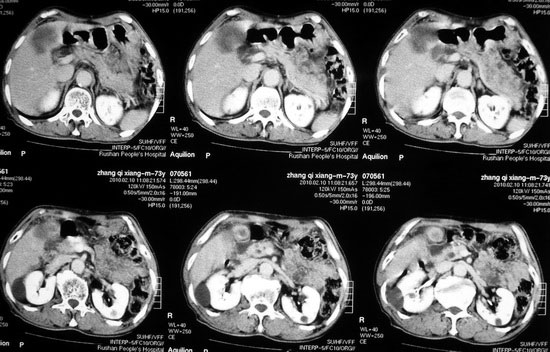

肝胆管细胞癌

患者AFP正常,无肝病病史。CA199 1000ng/ml,CEA偏高。血象WBC正常,N偏高。

化脓性胆囊炎累及肝脏;胆管细胞癌;肝转移瘤

活检病理

:是

胆管细胞癌

这个病人开始就是主要鉴别的肝脓肿和胆管细胞癌。可是增强后环征也不明显,占位内造影也非常不明显。这种情况怎么判断?谢谢大家。

病灶强化幅度较轻,低密度坏死区内见无定形高密度影,是其特点。